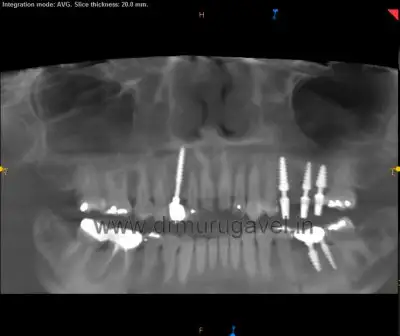

On Radiological Examination:

- On Radiological examination showing that missing teeth with bone loss & there was sufficient width & height present to place the implants.

Preoperative X-Ray

- It shows the missing teeth with bone loss & sinus drift but sufficient width & height present to place the implant on the left upper jaw.

- Healing of the implant is good which was done 3 years back in our clinic in the region of 13 & 36.

Postoperative X-Ray

- It shows the placement of 3 dental implants on the left upper jaw engaging the basal bone.